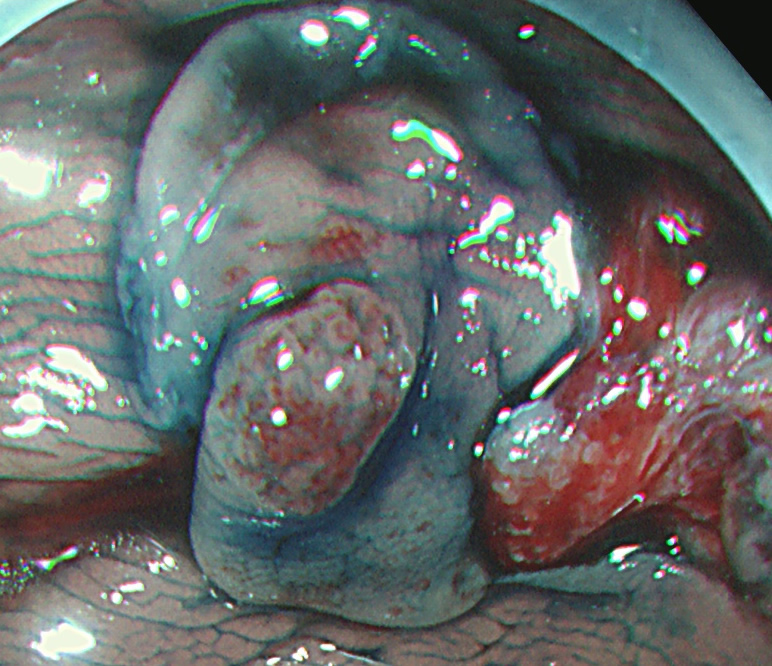

実際の写真です。

「生切り」なので、当然、内視鏡中(切除時)は出血します(患者さんが不安になります)。しかし、出血は数分で止まり、晩期出血は、まずありません。

取り残しを防ぐために、周囲に十分な余裕を持って大きく切除する必要があります(「ジャスト・サイズ」の傷では境界線上に腫瘍細胞が残ります)。そのために独特の「コツ」が必要で従来の方法よりも技術的に難しく時間がかかります。

意外に思われるでしょうが自験例では再発率は従来の電気メスを使用する方法より低いです。これは従来法では穿孔を恐れて十分に焼けない場合があるのに対ししてコールド法では穿孔の危険が無いために「徹底的に大きく・深く切除する」ことができるからです。